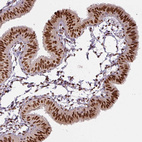

Immunohistochemical staining of human pancreas shows moderate nuclear positivity in exocrine glandular cells.